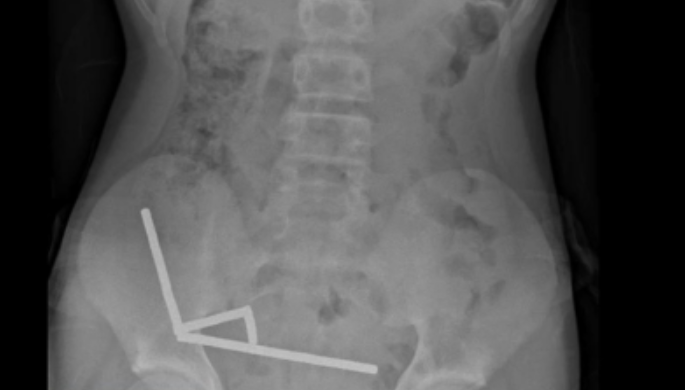

Exames revelaram que os ímãs haviam se agrupado em quatro correntes na parte inferior direita do abdômen, unindo diferentes seções do intestino com sua força magnética, segundo o relatório, que observou que algumas imagens foram distorcidas pelos ímãs. Os médicos então procederam com uma cirurgia exploratória.

Durante o procedimento, os cirurgiões descobriram que as correntes de ímãs estavam causando necrose por pressão – morte do tecido por pressão prolongada – em partes do intestino delgado e grosso. Eles conseguiram remover os ímãs, mas o menino precisou ter parte do intestino removido. Ele passou oito dias se recuperando no hospital antes de receber alta, informou o relatório.